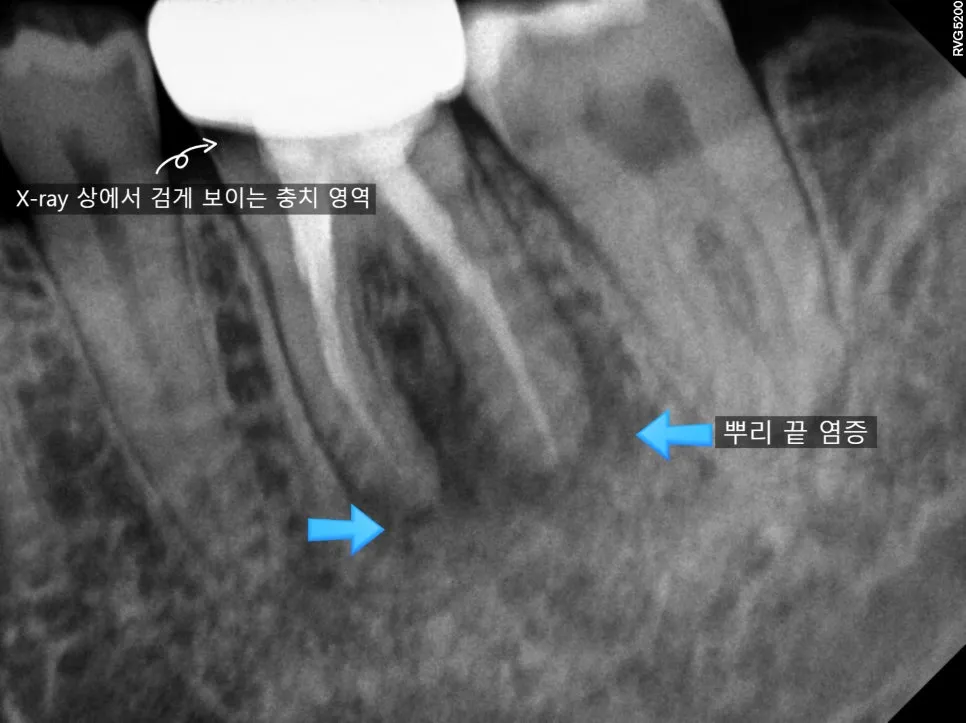

타 치과에서 발치 판정을 받고 내원하신 환자분의 케이스입니다. 기존 크라운이 탈락한 상태였고, 내부 상태가 좋지 않았습니다.

육안으로 보기에도 내부 오염이 심각하고 충치가 깊습니다. 단순히 다시 크라운을 씌우는 것으로는 해결되지 않습니다. 내부 충치를 제거하고, 뿌리 끝 상태를 확인해야 합니다.

엑스레이상 뿌리 끝에 염증이 보입니다. 이 경우 재신경치료가 필수적입니다. 다행히 뿌리에 금이 가거나 부러진 소견은 없어, 재신경치료를 시도해보기로 결정했습니다.